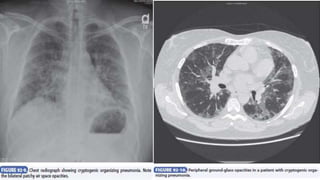

Cryptogenic Organizing Pneumonia

Cryptogenic organizing pneumonia, previously referred to as

Diagnosis

• Cryptogenic organizing pneumonia most commonly manifests as a

• Chest radiography reveals patchy unilateral or bilateral alveolar

opacities that may be peripheral or migratory; small nodular opacities

• In about 90% of patients, HRCT shows areas of air space consolidation

with lower lung zone predominance, frequently in a subpleural or

peribronchial distribution other features include small nodules along

bronchovascular bundles and ground-glass attenuation. BAL is

nonspecific; increased lymphocytes, neutrophils, and eosinophils may

be seen. On biopsy, key histologic features are excessive proliferation

of granulation tissue within the small airways and alveolar ducts as

well as chronic inflammation in the surrounding alveoli.